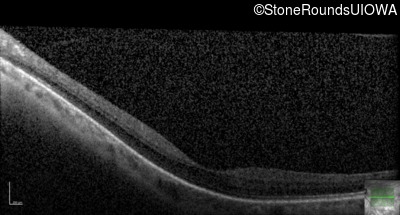

Optical Coherence Tomography - Right - 20/25 -3

Exemplar / OCT Stack